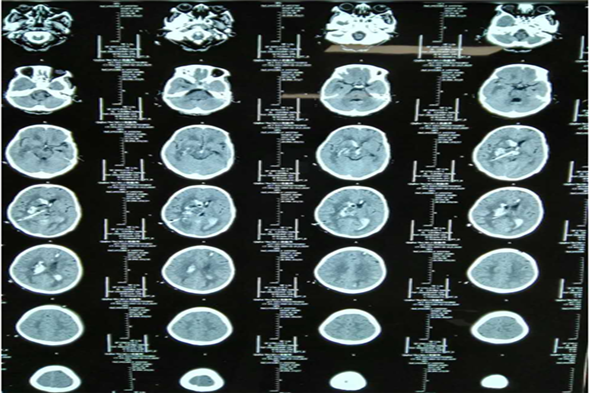

病例一 李某,男,35岁,脑出血、脑疝。

术前脑CT

术后三天脑CT

术后二周脑CT